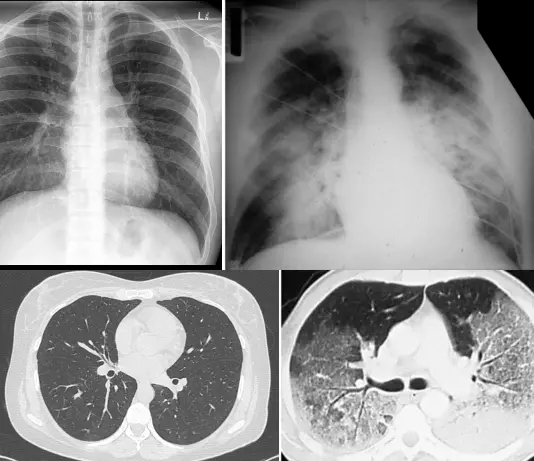

“白肺”是临床工作中的一个口语化描述,当患者肺部的炎症比较重,渗出液比较多时,肺部CT影像的白色区域达到75%以上,医务人员在临床上把它称为“白肺”。在感染新冠后,若出现咳嗽不断,胸闷气短,呼吸困难,可能是肺部出现炎症,需及时控制朝‘白肺’方向发展,日常可通过监测血氧饱和度来初步判断,若血氧饱和度小于93%,请立即前往医院进行进一步的检查。